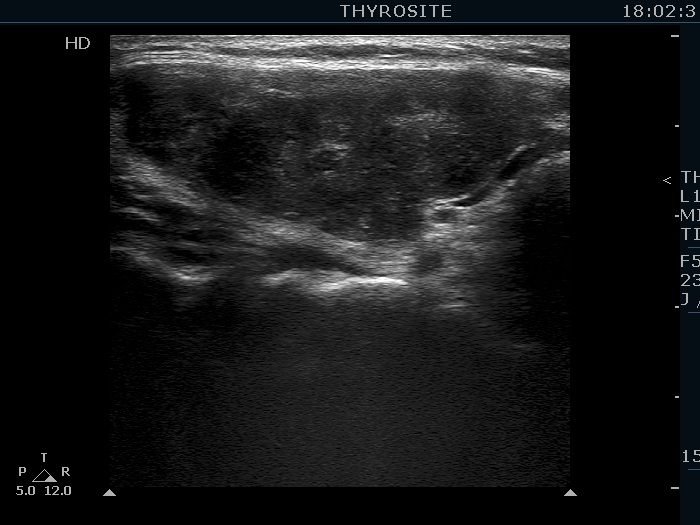

First examination (first row of images):

Clinical data: A 37-year-old woman requested an evaluation of complaints suggesting hypothyroidism. After her second birth two years ago, she was left with an excess weight of 18 kg.

Palpation: no abnormality.

Laboratory tests: TSH 3.52 mIU/L, FT4 14.1 pM/L, aTPO 405 U/mL.

Ultrasonography. The thyroid was echonormal and presented numerous hypoechogenic discrete areas. The echogenicity index was approximately 30%. None of the discrete areas corresponded to pathological nodule. The vascularity was a bit lower than the average.

Suggestion: TSH in a year.